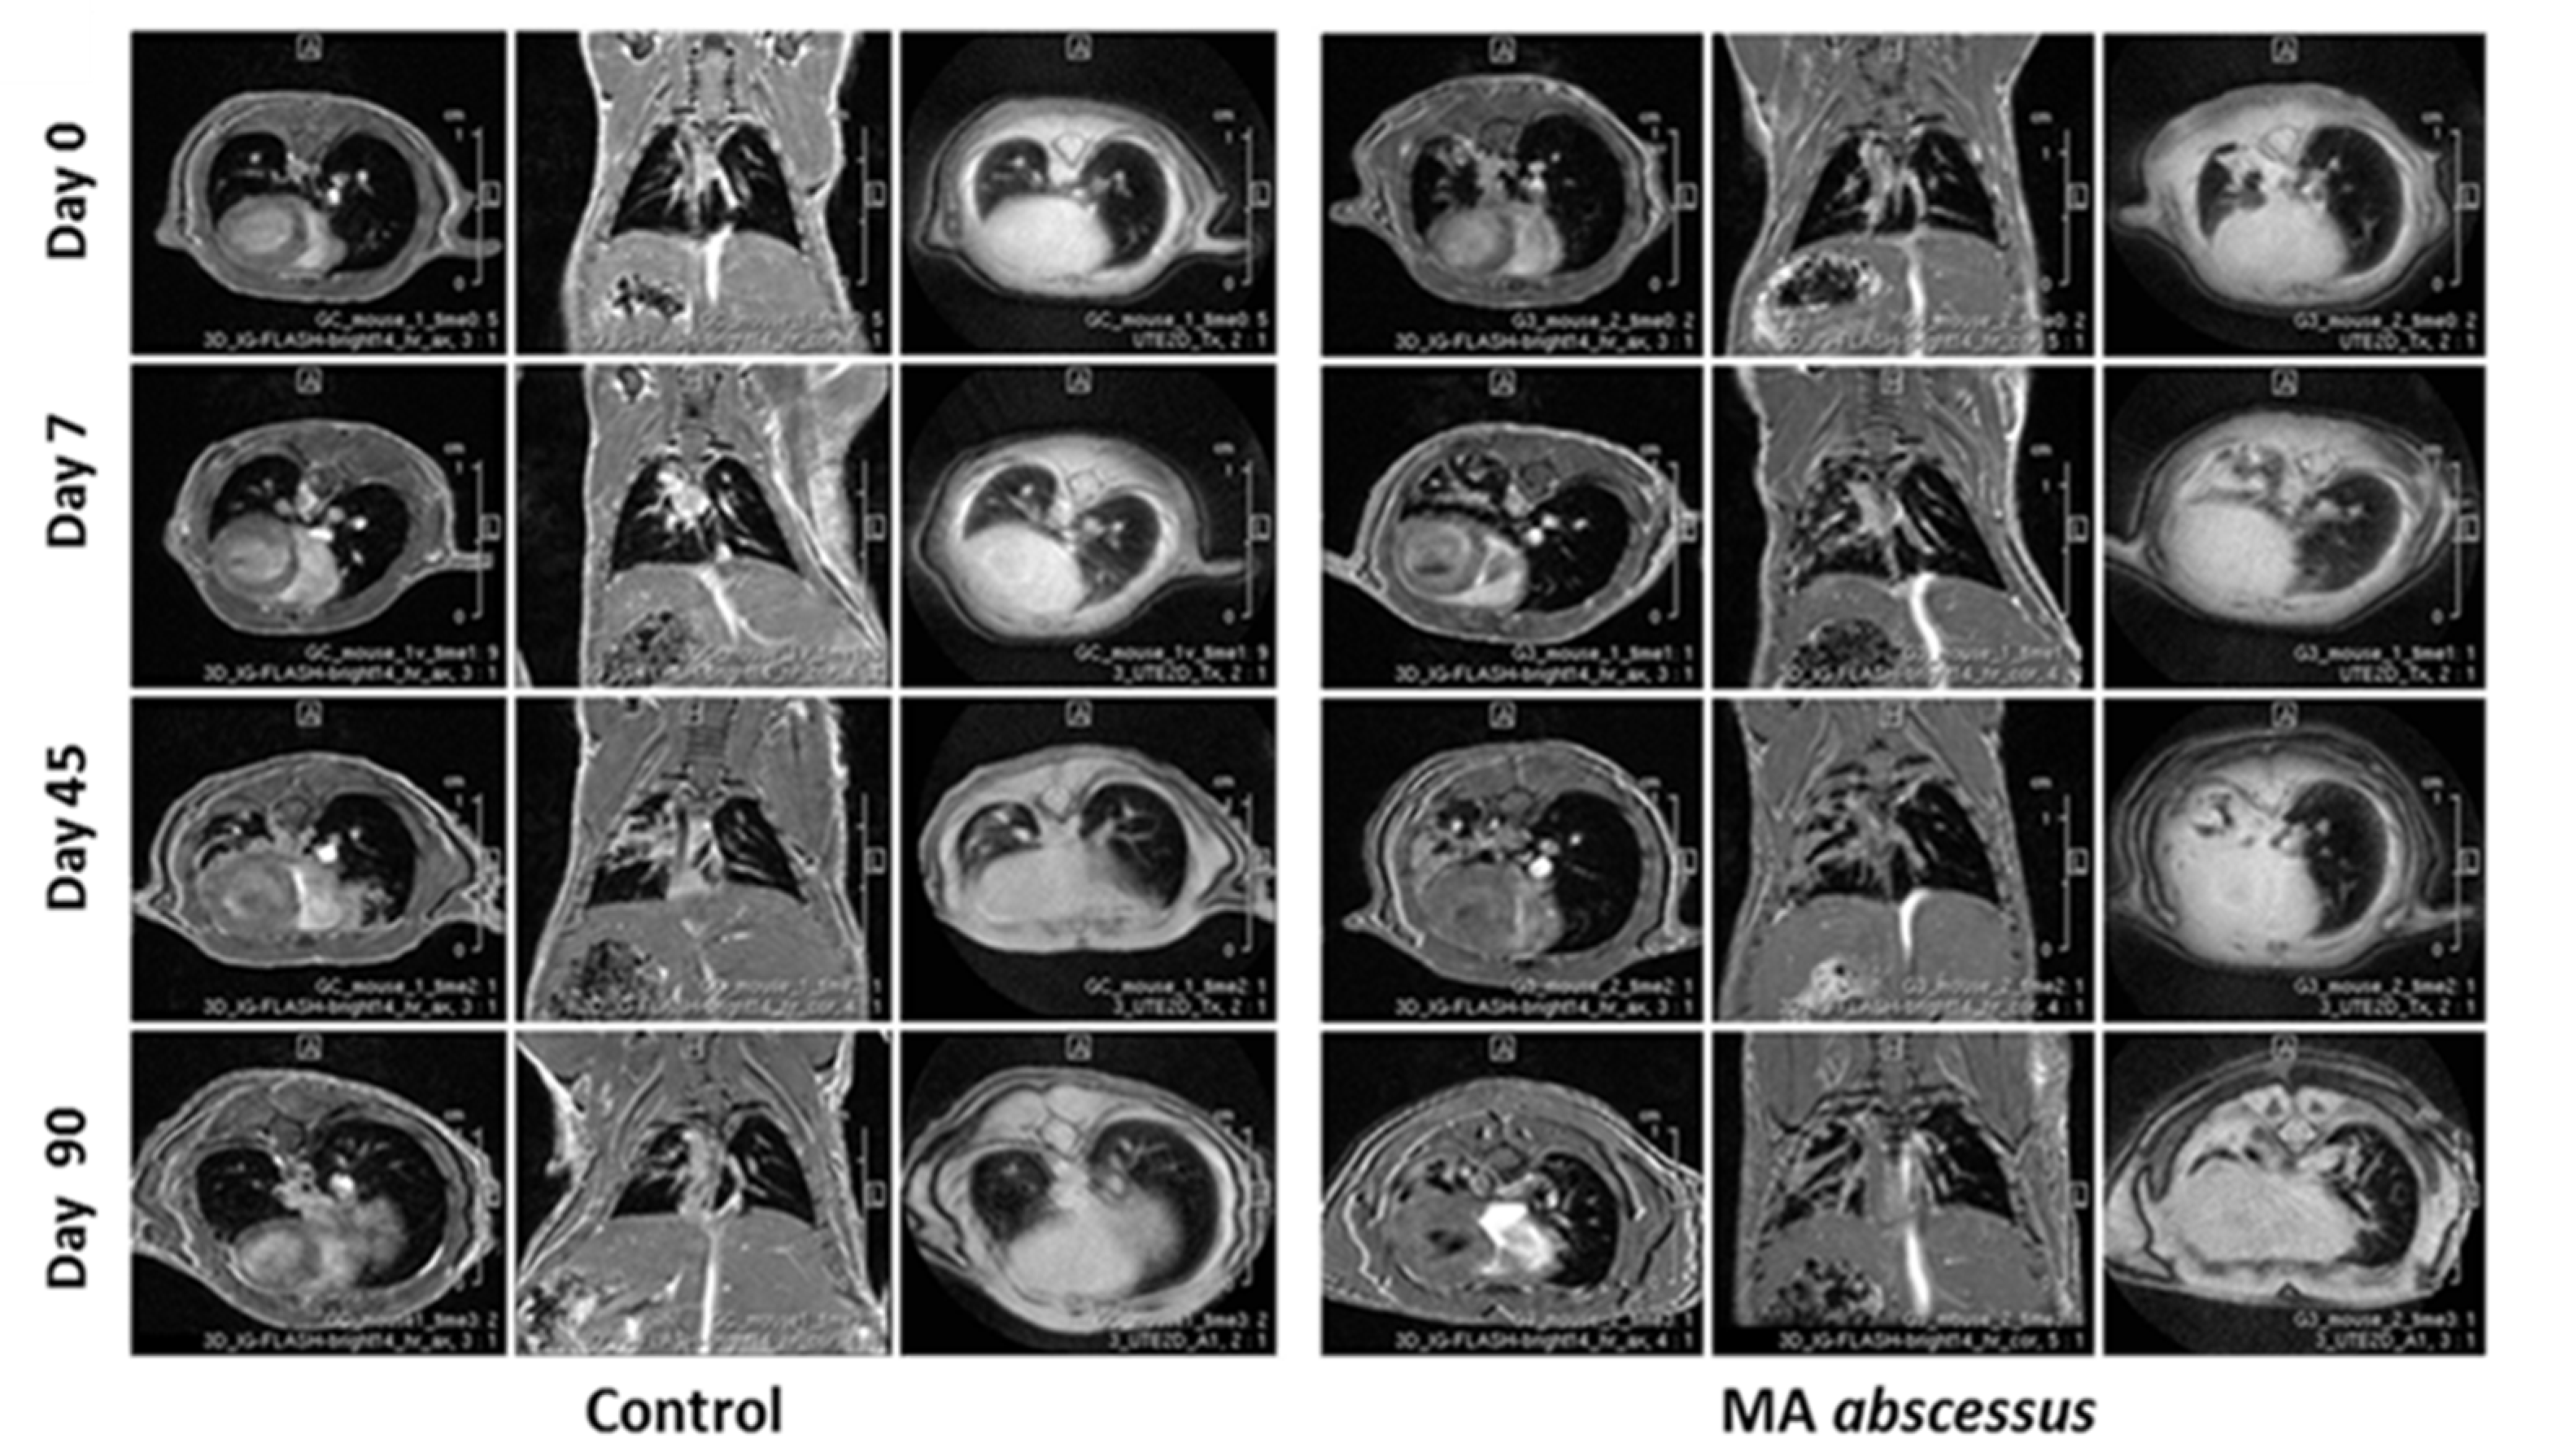

Longitudinal monitoring by MRI was introduced to evaluate the progression of the pulmonary lesions within single mice at the day of infection and at the time points of 7, 45, 90 days. Lesions induced by MA subsp. abscessus were clearly visible at the time points of 45 and 90 days. In particular, infection foci appeared as a round well-defined area of consolidation with a preferential distribution in the left lung (Figure 4).

Figure 4.

MRI analysis during the course of chronic MA subsp abscessus infection. Examples of representative axial and coronal 3D-FLASH and axial (2D-UTE) MR images of single mice lungs obtained after inoculation with sterile agar beads (control mice) and with MA subsp. abscessus. The two mice (control mice and infected mice) monitored by MRI over time were always the same from Day 0 to Day 90.

The emerging problem of MA infections in the last 20 years has focused attention on the understanding of the pathogenesis of MA disease, which remains inadequately characterized [18]. Our aim was to develop an immunocompetent mouse model overcoming MA clearance and miming human MA airway disease (e.g., CF, COPD, bronchiectasis or asthma). We performed intratracheal infection in C57BL/6NCrl mice, known as resistant to mycobacterial infection, with MA entrapped in small agar beads. This method was refined from the original protocol established by Bragonzi et al. successfully used to study P. aeruginosa, B. cepacia and S. aureus infection and co-infections [15,16,17]. So far, C57BL/6NCrl mice were characterized by efficient clearance of MA from the lungs when inoculated via aerosol at a low dose; in contrast, airways clearance was much less effective following inoculation of high intravenous doses, ranging from 106 to 108 CFU [19,20]. Furthermore, male C57BL/6NCrl mice are described as developing more severe lung lesions and having greater mortality with mycobacterial infection than female C57BL/6NCrl mice [21]. Embedding MA within agar beads and using intratracheal injection physically retained the bacteria in the bronchial airways and provided microanerobic/anaerobic conditions that allow bacteria to grow in microcolonies [22]. This procedure allowed us to create a stable infection in immunocompetent male mice with all the three MA subspecies, and to reproduce a chronic infection useful for studying pathogenesis and progression of MA lung disease until three months from the inoculum. In particular, the chronicity breakpoint was, for MA subsp. abscessus, 65 days and, for MA subsp. bolletii and MA subsp. massiliense, 45 days; after such time points, mice progressively inclined to clear the infection. Very recently, Le Moigne [23] have published that intratracheal infection with agar beads is associated with very high mortality, in our hands the mortality has been very low and the chronicity was successfully established. In human hosts, MA can persist silently for years, and even decades, and can induce organized granulomatous lesions with foamy cells and in some cases, even caseous necrosis, like M. tuberculosis [24]. Infection with intracellular pathogens like MA is effectively controlled by the cell-mediated immune response and several cytokines play important roles limiting the host inflammatory response. In particular, IFN-γ is critical in the immune response to MA infection: it activates infected macrophages in concert with TNF-α and initiates a major effector mechanism of cell-mediated immunity. Immunocompetent mice, with evidence of strong TH1 response [25], appear resistant since they are characterized by a transient lung infection with a rapid clearance of MA in the first weeks [8,9,10]. Several attempts, with the aim of slowing down the resolution of MA lung infection, have led to establishing mouse models with deficits in innate or acquired immunity (e.g., GM-CSF -/, GKO or SCID mice) [11,12,13]. Moreover, corticosteroids were recently administered to immunocompetent mice to increase their susceptibility to the aereosolized pulmonary MA infection [26]. In our murine model, despite an initial protective high release of TNF-α and IFN-γ, granuloma-like lung lesions (characterized by aggregates of histiocytes, a few neutrophils, and lymphocytes) were present around bronchi involving surrounding parenchyma for about two months after MA infection, likely mimicking the damage observed in humans [24]. Interestingly, the presence of vaculated histiocytes, reported previously only in immunocompromised mice (SCID mice and GM-CSF -/- mice) [12], highly supports the reliability of this model with immunocompetent mice. For the first time, we introduced the monitoring of the MA lung infection with the MRI technique in this study. MRI represents a non-invasive approach providing an excellent qualitative evaluation for the assessment of inflammatory soft-tissue diseases in both humans and small laboratory animals [27], as well as an effective tool for monitoring lung inflammatory processes [28], without the possible detrimental impact on the immune system related to the use of X-ray-based imaging approaches like Computed Tomography. MRI was applied in longitudinal measurements to monitor changes in infectious lesions, within the same C57BL/6NCrl mice, at the day of infection and after 7, 45, and 90 days from infection. Despite the decrease in pro-inflammatory markers and the dissolutions of granuloma-like lesions during the course of the infection, the murine lung parenchyma was still damaged at 90 days, as observed following both histopathological and MRI analysis, indicating a correlation between the two techniques. MRI was also able to discriminate, as with the histopathological analysis, the lung inflammatory foci, induced by empty beads in control mice presenting as microscopic areas of consolidation at day 45 and 90.